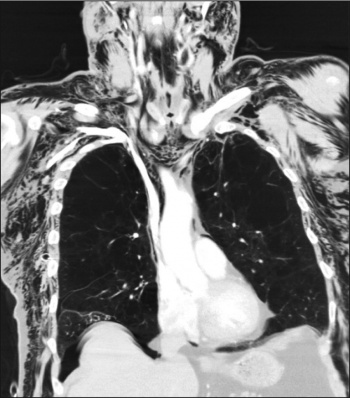

Figure 2. A CT chest with contrast showed a 13x10x12cm cavitating lesion predominantly in the right upper lobe

Figure 2. A CT chest with contrast showed a 13x10x12cm cavitating lesion predominantly in the right upper lobe(click to enlarge)

A CT chest with contrast was performed which showed a 13x10x12cm cavitating lesion with a large air/fluid level predominantly in the right upper lobe (see Figure 2). Associated with it, there was prominent reactive adenopathy in the superior, anterior mediastinum, as well as in the subcarinal position (see Figure 2).

A CT-guided biopsy confirmed a methicillin-resistant Staphylococcus aureus-positive lung cavitation, most likely secondary to his poor dentition. A full dental clearance was performed, and he was treated with a course of intravenous vancomycin and oral clindamycin with good effect.